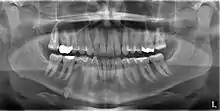

An impacted tooth is one that fails to erupt into the dental arch within the expected developmental window. Because impacted teeth do not erupt, they are retained throughout the individual's lifetime unless extracted or exposed surgically. Teeth may become impacted because of adjacent teeth, dense overlying bone, excessive soft tissue or a genetic abnormality. Most often, the cause of impaction is inadequate arch length and space in which to erupt. That is the total length of the alveolar arch is smaller than the tooth arch (the combined mesiodistal width of each tooth). The wisdom teeth (third molars) are frequently impacted because they are the last teeth to erupt in the oral cavity. Mandibular third molars are more commonly impacted than their maxillary counterparts.

Classifications enable the oral surgeon to determine the difficulty in removal of the impacted tooth. [9] The primary factor determining the difficulty is accessibility, which is determined by adjacent teeth or other structures that impair access or delivery pathway. The majority of classification schemes are based on analysis on a radiograph. The most frequently considered factors are discussed below.

This type of classification is based on the amount of impacted tooth that is covered with the mandibular ramus. It is known as the Pell and Gregory classification, classes 1, 2, and 3.[10]

Relationship of tooth to occlusal plane

The depth of the impacted tooth in relation to the adjacent second molar serves as the foundation for this type of classification. This was also given by Pell and Gregory and is known as the Pell and Gregory A, B, and C classification. Relationship to the occlusal plane A-C classes